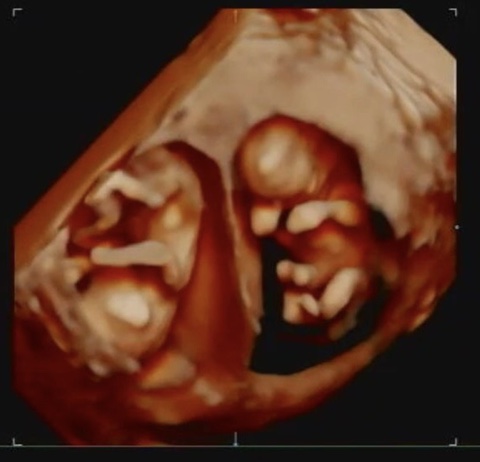

임신일기 ep8 - 쌍둥이 임신 20~21주/임신중반 증상/조리원 결정

20주가 됐다. 뭔가 상징적이다. 한번 화유를 겪고 나서 임신을 유지한다는게 어렵다는 걸 뼈저리게 느꼈고 ...